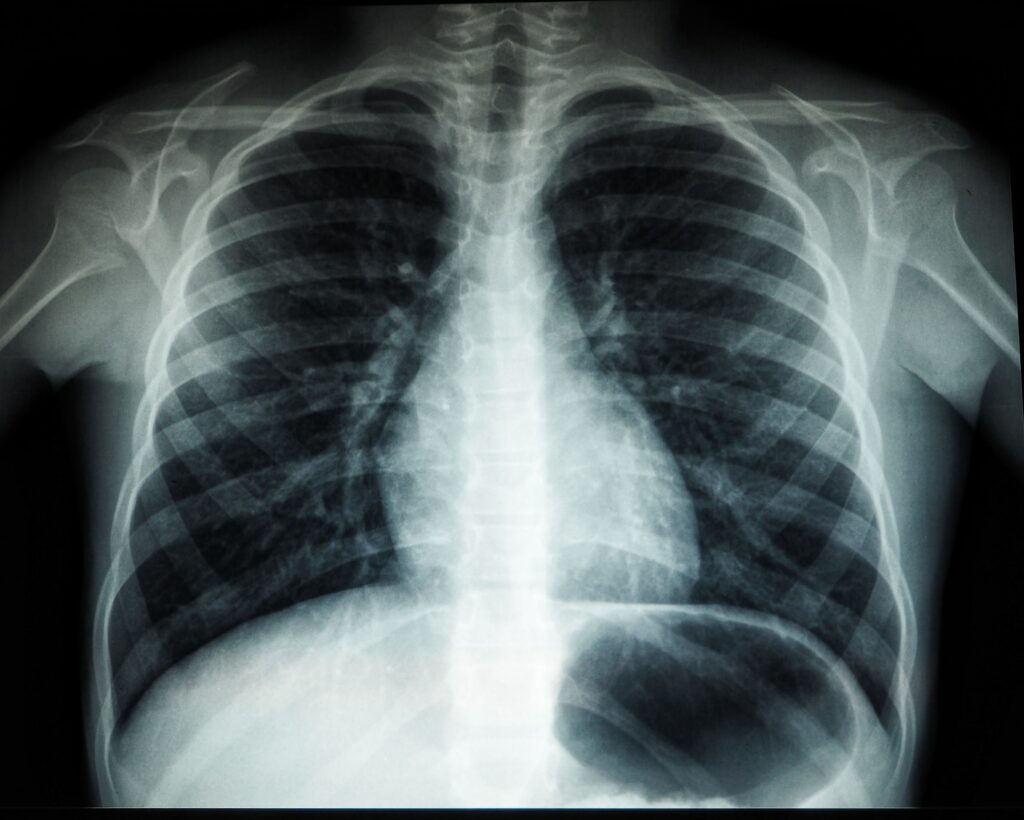

CES 2024, themed “AI in Everything,” has prompted various industries to explore interdisciplinary integration, with the AI medical sector serving as a prominent example. Moderna, a pharmaceutical tech giant, has …